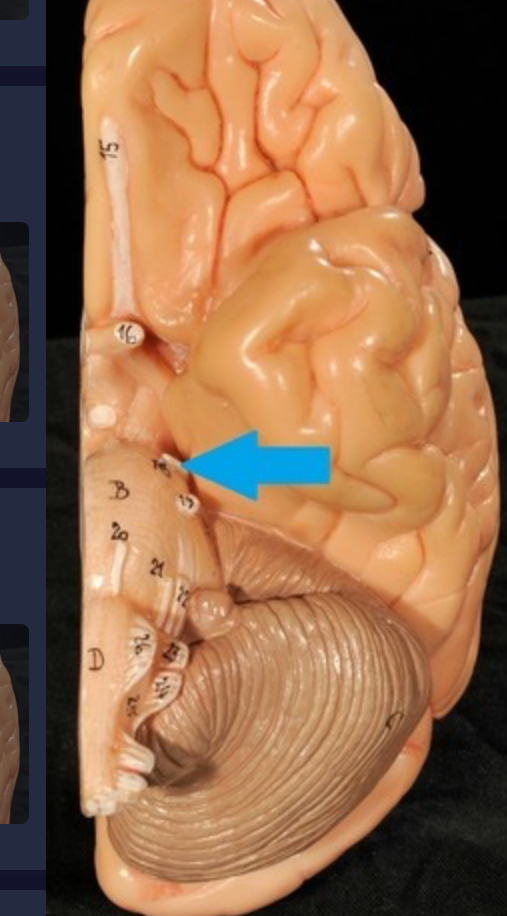

I. Olfactory

II. Optic

III. Oculomotor

IV. Trochlear

V. Trigeminal

VI. Abducens

VII. Facial

VIII. Vestibulocochlear

IX. Glossopharyngeal

X. Vagus

XI. Accessory

XII. Hypoglossal